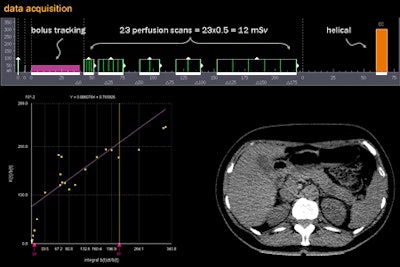

Multiple protocol design possibilities are used at Rogalla's institution. Commonly, they begin with a bolus tracking sequence to catch the arterial inflow, followed by a certain number of perfusion scans, followed by a diagnostic helical acquisition.

![]() |

| The acquisition shown above includes 23 perfusion scans, each providing a radiation dose of 0.5 mSv, for a total of 12 mSv plus a diagnostic scan at the end. The Patlak plot (below, left) provides a trend line from which perfusion values can be read directly. Reducing the number of perfusion scans is a workable option depending on the organ and diagnostic needs, but it can also reduce the reliability and reproducibility of the results. |